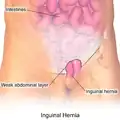

| Diagram of an indirect, scrotal inguinal hernia (median view from the left). | |

Illustration of an inguinal hernia.

Illustration of an inguinal hernia. -